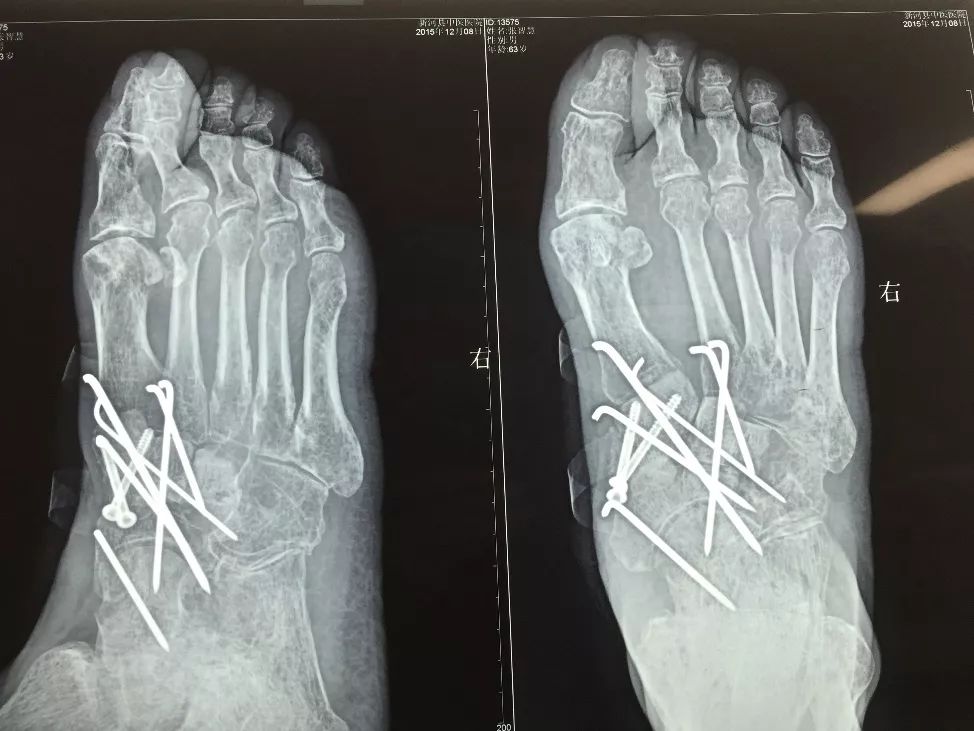

下面1例是我的学生所发。病史清楚,跗骨骨折后伤口开放,每次换药用双氧水冲洗伤口,造成骨坏死

跗骨感染

该例患者需要汲取的经验和教训:不要使用双氧水冲洗伤口死骨密度高是因为不参与代谢周围骨疏松治疗清理死骨后用骨水泥诱发诱导模反复几次做半开放植骨手术后走路刺激骨愈合,改善骨质愈合。